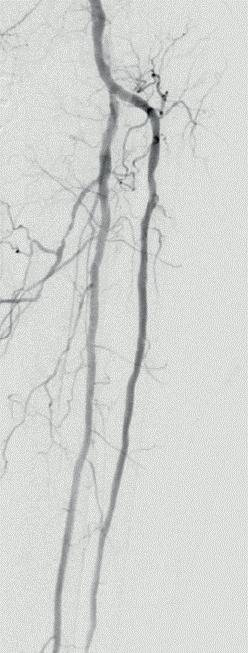

Figure 1: Diffuse calcified occlusive disease on pre-procedural arteriogram

a) Anterior tibial (AT) artery b) Dorsalis pedis (DP) artery

Figure 2: Shockwave Javelin in therapy a) In the AT b) In the DP

Figure

3: Definitive therapy, AT and DP treated with a 2.5x150mm angioplasty balloon a) Completion angiogram of AT b) Completion angiogram of DP

However, after more experience Foley has found Shockwave Javelin’s role to be more nuanced and depends on the vessel bed, he says. In the femoropopliteal space, the Shockwave Javelin works best as facilitator, “modifying calcium to facilitate the next step”. In the tibial vessels, Foley continues, a good outcome is defined as successfully

crossing the lesion while delivering pulses. “I don’t see Shockwave Javelin simply as a method of crossing the uncrossable anymore; I see it as way more than that. When I look at a calcified, highly stenotic tibial vessel, Shockwave Javelin is now my knee-jerk device.” Below the ankle, Foley says, the Shockwave Javelin is breaking new ground by effectively crossing through vessels previously unpassable by any other method.